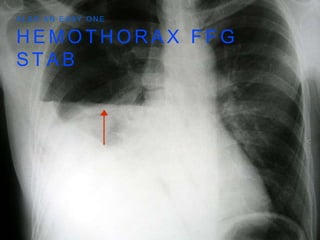

P T W I T H A S T A B T O L E F T C H E S T W A L L

H E MO T H O R A X F F G S T A B A L S O A N E A S Y O N E